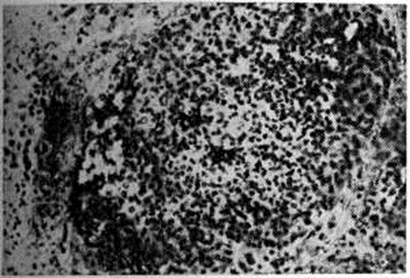

Гистологический картина изменений в метастатических очагах различных органов и тканей не имеет строго выраженных специфических черт. В начальной стадии кандидозного процесса наблюдается некротически-экссудативная воспалительная реакция, чаще гнойного характера, реже с преобладанием в инфильтрате лимфоцитов. Интенсивность разрастания грибка зависит от жизнеспособности ткани: там, где некроз выражен резче, нитей грибка значительно больше. При хронический течении процесса вокруг некротически-экссудативного очага воспаления происходит разрастание соединительной ткани или наблюдается формирование гранулемы (смотри полный свод знаний), напоминающей таковую при туберкулёзе (рисунок 3). Ликвидация грибка в организме происходит в основном за счёт лизосомальных ферментов сегментоядерных лейкоцитов (рисунок 4), то есть в результате так называемый внеклеточного фагоцитоза, поэтому рост грибка в гнойном очаге обычно тормозится. Присутствие большого количества сегментоядерных лейкоцитов препятствует размножению грибка, лейкоциты как бы облепляют элементы грибка и, подвергаясь распаду, отграничивают его от окружающей ткани (рисунок 5). Как показывают электронно-микроскопические исследования, в клетках грибка нарушается целостность цитоплазматической мембраны и появляются аутофагические вакуоли в цитоплазме. Фагоцитоз грибков сегментоядерными лейкоцитами встречается редко и касается в основном нежизнеспособных клеток грибков; в цитоплазме же макрофагов (рисунок 6) и гигантских клеток грибок может находиться длительное время и быть жизнеспособным — так называемый эндоцитобиоз. Поскольку грибок способен к внутриклеточному паразитированию, то наличие его жизнеспособных форм свидетельствует о том, что воспалительный процесс имеет затяжной характер.

Рис. 6. | ||